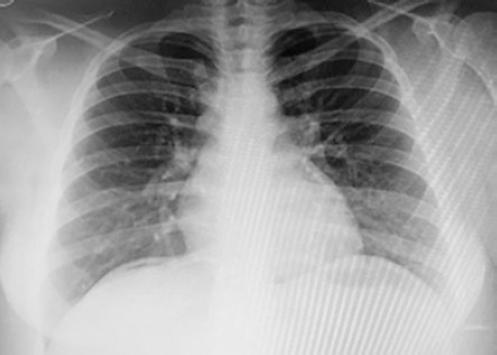

En la exploración física muestra una presión arterial de 110/70 mmHg, una frecuencia cardiaca de 110 latidos por minuto y una frecuencia respiratoria de 20 *min. A la inspección el abdomen es globoso, no se auscultan soplos, y presenta dolor a la palpación profunda en el epigastrio sin signos de irritación peritoneal. Se le realiza radiografía de tórax en la que se evidencia neumoperitoneo en el espacio subdiafragmático derecho (Fig. 1).

Figura 1 Radiografía de tórax en la cual se evidencia neumoperitoneo en el espacio subdiafragmático derecho.